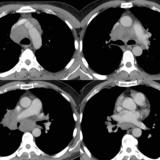

Gallery Lung Cancer SCLC

SCLC

Case 1a